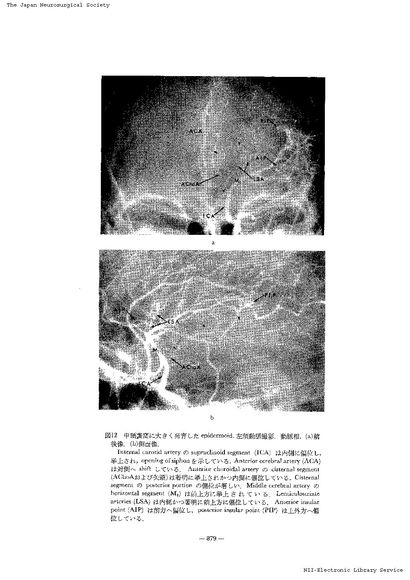

第3脳室近傍腫瘍の神経放射線診断-脳血管撮影を中心に- III 主に第3脳室の側方に発育する腫瘍(2)